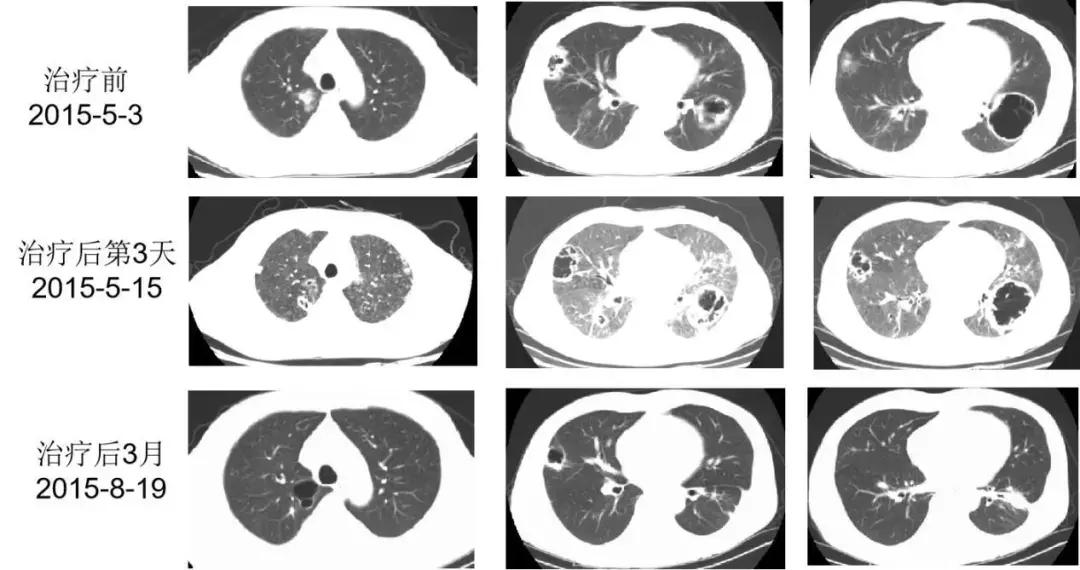

2015-5-15(入院后第9天)抗奴卡菌治疗第3天,患者诉右侧胸痛较前有所缓解,但感呼吸困难,咳嗽、咳痰好转不明显,查体:双肺散在哮鸣音,血气分析(吸氧2L/min):pH 7.48,PaO2 60.3mmHg,PaCO2 28.8mmHg,HCO3- 21.7mmol/L。

患者症状明显好转,血气分析恢复正常,胸部CT双肺空洞较前好转,于2015-5-29安排患者出院。出院带药:复方磺胺甲噁唑 1.44g q6h、伏立康唑 200mg bid、甲泼尼龙20mg qd,出院后予伏立康唑治疗2周后患者自行停药(抗真菌治疗共3周余),继续复方磺胺甲噁唑 1.44g q6h+甲泼尼龙20mg qd治疗。

该患者治疗后经连续动态的观察发现肺部病灶在缩小、好转,临床疗效明确。虽然抗真菌治疗共3周,但有机体免疫功能逐渐恢复的背景,所以疾病不会进展。